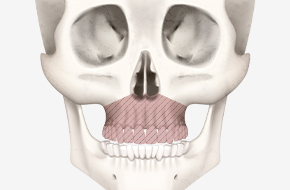

양악수술은 상악(윗턱)과 하악(아래턱)을

동시에 교정해 턱뼈 성장 이상, 부정교합,

턱관절 장애 등을 바로잡고

기능을 개선하는 수술입니다.

상악과 하악을 절골합니다.

절골된 상악과 하악을

수술 계획에 맞게 이동하여

교합을 맞춥니다.

절골된 뼈를 단단히 고정해

움직이지 않도록 하여,

올바른 교합과 조화로운 얼굴로 완성합니다.